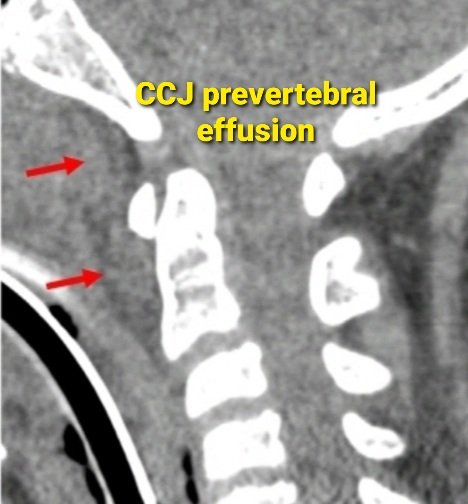

🔷90% of Anterior altlanto occipital membrane tears present with prevertebral effusion 🔷Prevertebral efffusion in screening CT in high velocity trauma patient➡️ Recommend cervical spine MRI @vebinars_neuro #NeuroRad #spinerad #radres #foamrad #Neurosurgery #spinesurgery

🤷‍♂️ Why care about Anterior Atlanto-Occipital Membrane (AAOM) tears? ✅ Routinely visible on #MRI ✅ Tears in 3️⃣ distinct patterns ✅ Presents w/ CCJ prevertebral effusion on #CT & major CCJ lig. injuries on #MRI ➡️ rdcu.be/dawhs #NeuroRad #NeuroSurgery #Spine

PeteFiesterMD's tweet image. 🤷‍♂️ Why care about Anterior Atlanto-Occipital Membrane (AAOM) tears?

✅  Routinely visible on #MRI

✅  Tears in 3️⃣ distinct patterns

✅  Presents w/ CCJ prevertebral effusion on #CT & major CCJ lig. injuries on #MRI

➡️ rdcu.be/dawhs

#NeuroRad #NeuroSurgery #Spine